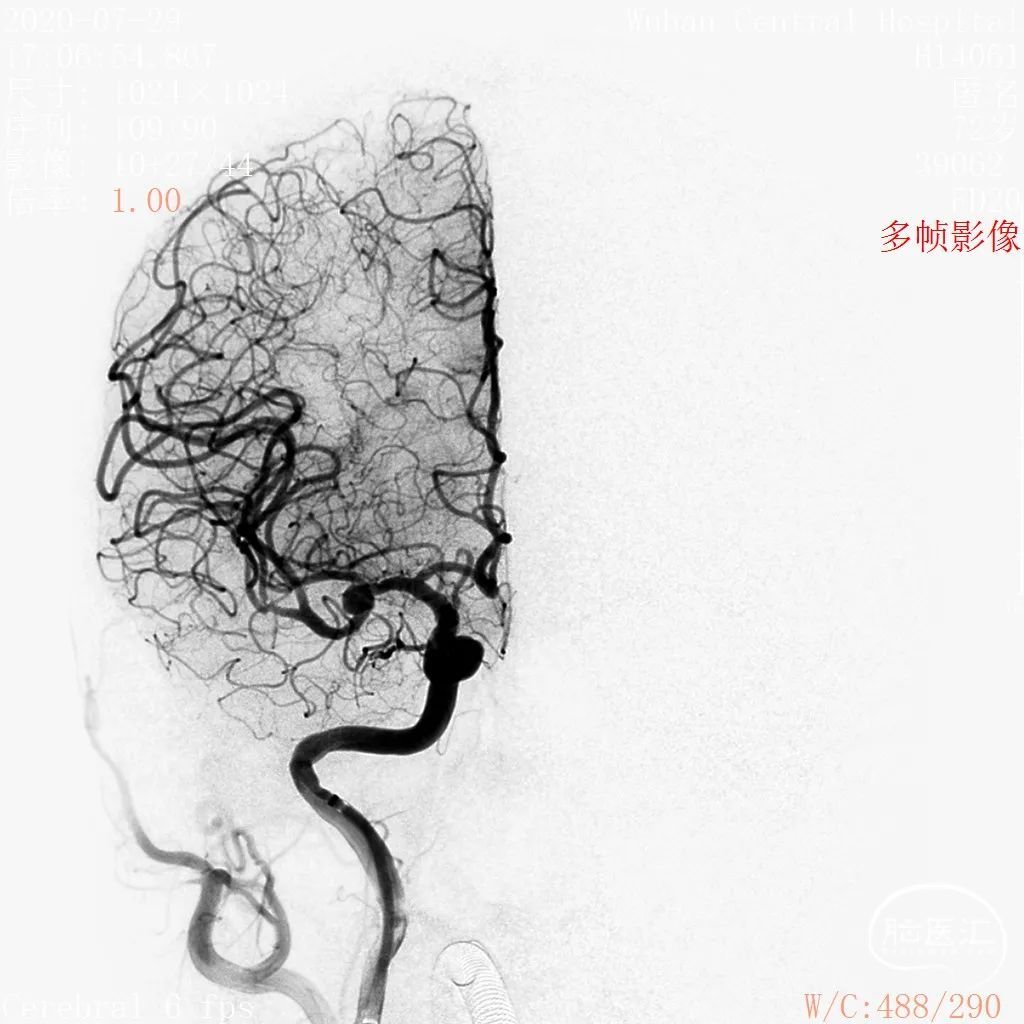

术前影像

DSA 2020-07-29